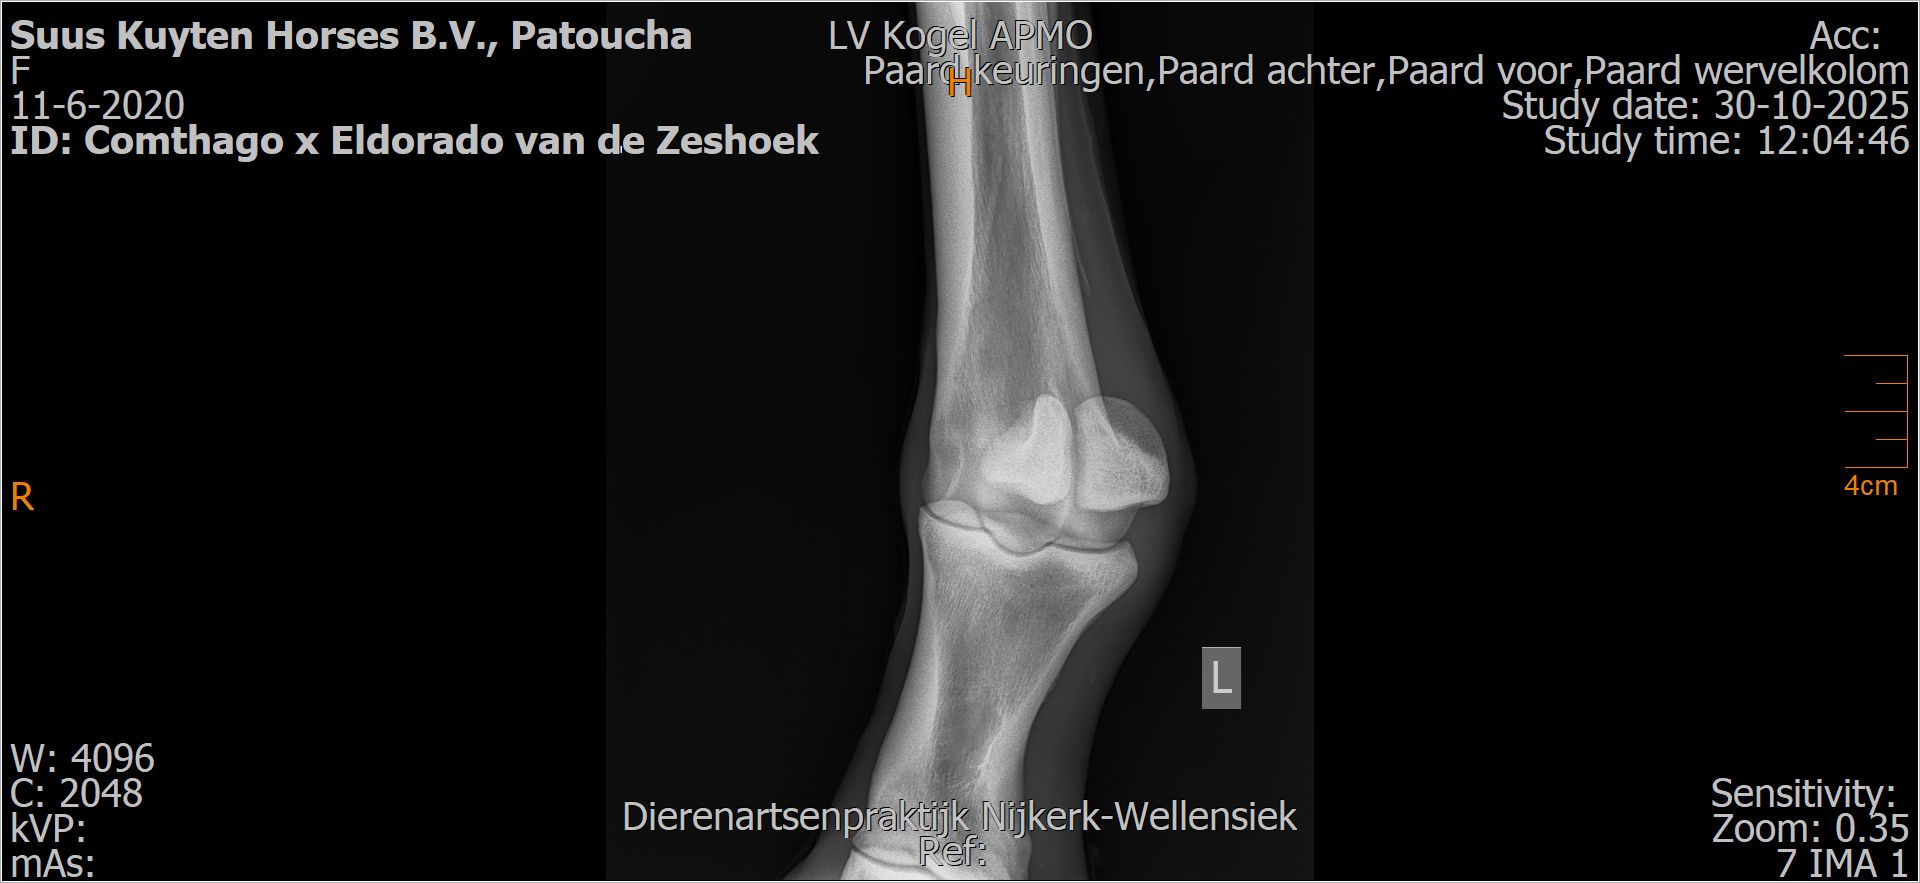

Patoucha

Leeftijd:

7

Röntgenfoto’s